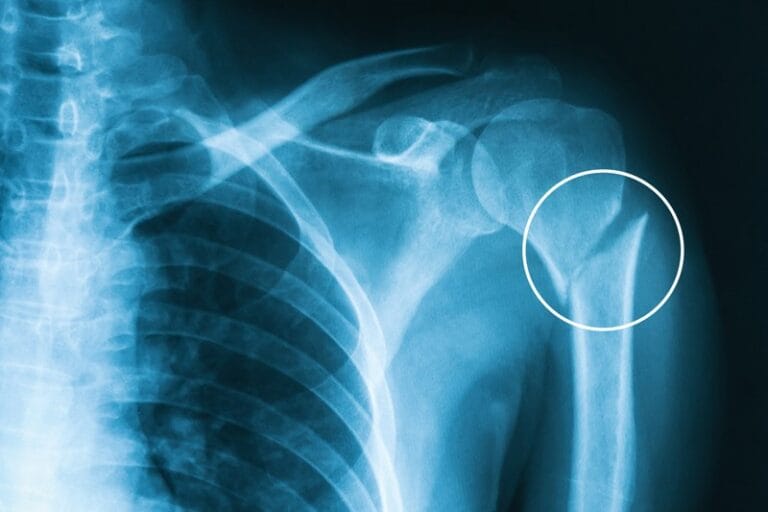

- Imaging: X-rays may not reveal a stress fracture initially. An MRI or bone scan is more effective in identifying early-stage stress fractures